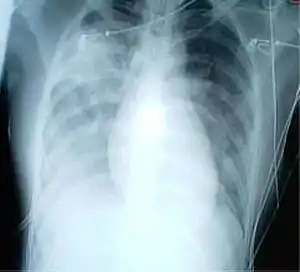

Une radiographie pulmonaire montrant des opacités dans les deux poumons, indicatives d'une pneumonie, chez un patient atteint de SRAS.

Radiologie

L’imagerie radiologique occupe une place importante dans le diagnostic initial de syndrome respiratoire aigu sévère puis dans le suivi de l’efficacité du traitement. Les images les plus typiques comportent une localisation périphérique prédominante, des opacités alvéolaires unilatérales et focales progressant sous traitement vers une atteinte unilatérale multifocale ou bilatérale. Il n’existe ni excavation, ni adénopathie, ni épanchement pleural. Le scanner thoracique est un examen complémentaire qui permet en général de préciser les signes de pneumopathie sévère.